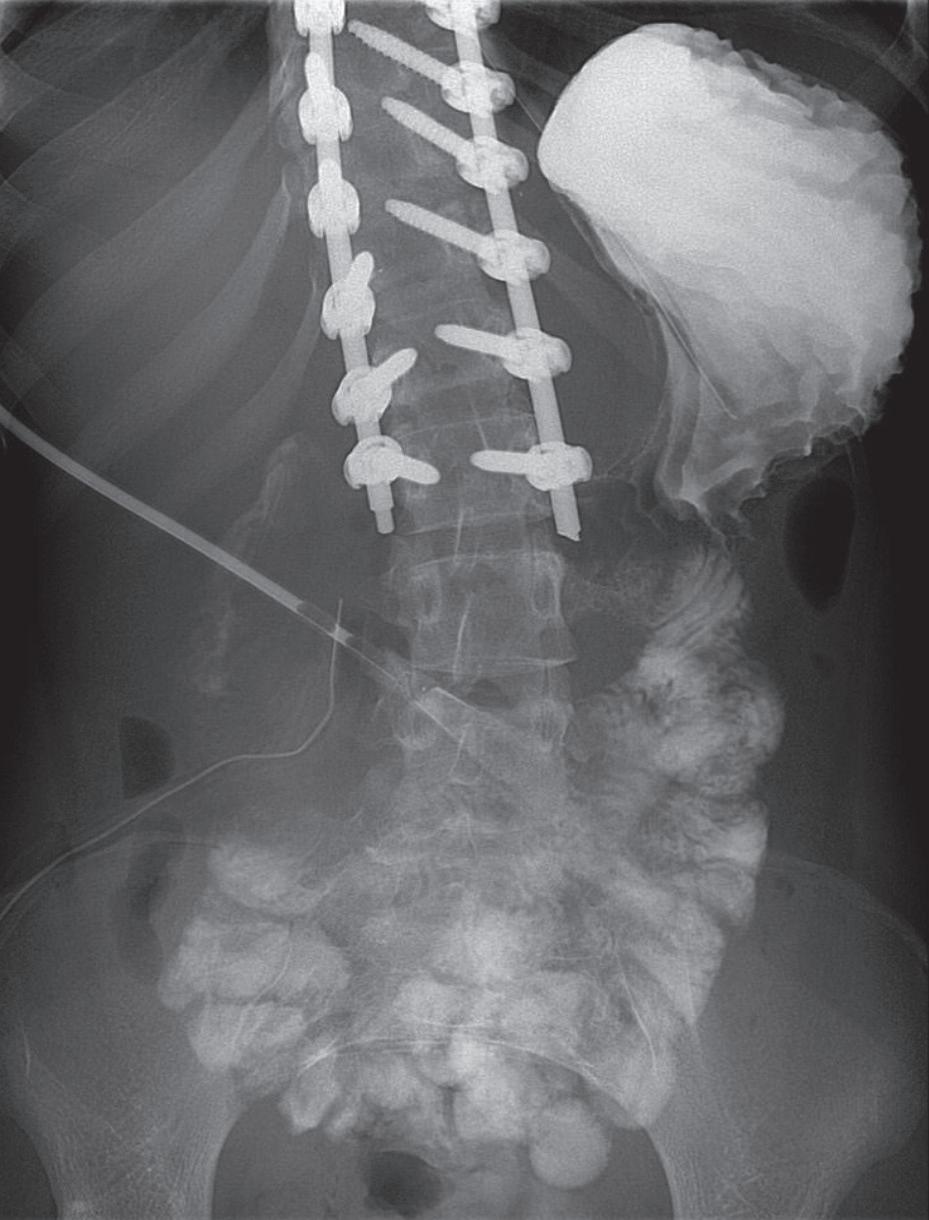

G., 16 anni, affetta da grave scoliosi idiopatica, giunge in Italia dalla Costa d’Avorio per eseguire correzione chirurgica di tale difetto. Dopo 9 giorni dall’intervento numerosi episodi emetici con addominalgia diffusa; non febbre, alcune evacuazioni diarroiche. All’arrivo in pronto soccorso: PV nella norma, paziente sofferente, pallida, diffusa dolenzia addominale, restante EO nei limiti. Agli esami ematici: GB 21.000/uL, N 91,4%, PCR 26,4 mg/dL; all’ecografia addominale distensione gastrica e intestinale a contenuto liquido. In seconda giornata, dopo iniziale miglioramento, ripresa dell’algia addominale con tre ulteriori episodi emetici. Nel sospetto di quadro occlusivo si eseguivano RX addome [Figura 5]: livelli idroaerei gastrici e in ipocondrio dx, in assenza di aria libera; TC addome [Figura 6]: marcata gastrectasia a contenuto fluido con dilatazione duodenale fino al Treitz. Si applicava sondino naso-gastrico con aspirazione di 400 ml di contenuto maleodorante; la successiva RX prime vie digerenti con m.d.c. confermava l’occlusione duodenale [Figura 7]. Alla laparotomia urgente, per evidenza di compressione ab estrinseco del duodeno da parte dell’arteria mesenterica superiore (AMS) [Figura 8], venivano eseguite resezione e anastomosi duodeno-digiunale. All’RX post-intervento con m.d.c. normale transito intestinale [Figura 9]. La causa del quadro occlusivo era data dalla sindrome del compasso aorto-mesenterico (SCAM) correlata alla recente artrodesi.

Figura 5. Esame radiografico diretto dell’addome pre-intervento Figura 6. Tomografia assiale computerizzata dell’addome pre-intervento Figura 7. Radiografia diretta dell’addome con mezzo di contrasto idrosolubile pre-intervento

Nel caso in esame la rettilineizzazione della colonna ha determinato un “effetto pinza” sul duodeno. Tra le cause principali: perdita di peso rapida e importante (anoressia nervosa); anomalie congenite dell’emergenza dell’AMS; eccessiva lordosi lombare; ptosi viscerale; trazione esercitata sull’AMS da un mesentere eccessivamente breve, ecc. La presentazione clinica tipica include: nausea, vomito, dolore e distensione addominale, ridotta intensità dei borborigmi [1]. Il sospetto clinico viene solitamente corroborato da esami di imaging (studi contrastografici con evidenza di blocco del transito intestinale a livello duodenale); lo studio angiografico è il gold standard nel definire con precisione l’angolo aorto-mesenterico [2]. Il trattamento è conservativo oppure chirurgico; le indicazioni

verso l’uno o l’altro approccio sono oggetto di discussione sia per i tempi sia per le modalità [2].

La SCAM è storicamente legata agli interventi chirurgici per scoliosi; analisi dettagliate della letteratura sono state condotte [3], ma solo di recente una review sistematica (52 casi in circa 50 anni) ha puntualizzato alcuni aspetti [4]: in particolare l’età media dei pazienti con SCAM post-intervento per scoliosi è 14,7 ± 2,9 anni e vi è una netta prevalenza femminile (80,8%). L’intervallo tra l’intervento e l’inizio della sintomatologia relata alla SCAM è di 9,6-9,5 giorni. I sintomi più comuni sono vomito (92,3%), nausea (50%), dolore (48,1%) e distensione addominale (40,4%).